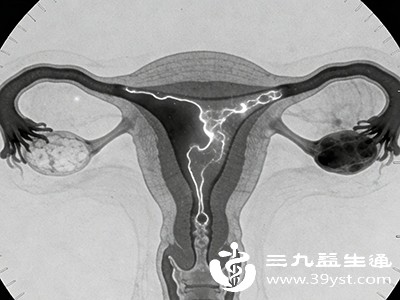

对于中重度堵塞,尤其是近端堵塞(靠近子宫一侧),可通过宫腔镜下输卵管插管疏通术治疗;远端堵塞(靠近卵巢一侧)常伴随粘连,腹腔镜手术是常用的治疗方式,医生会在镜下分离粘连、修复输卵管形态。如果堵塞严重、输卵管功能已完全丧失,辅助生殖技术(如试管婴儿)则是实现生育的有效选择。